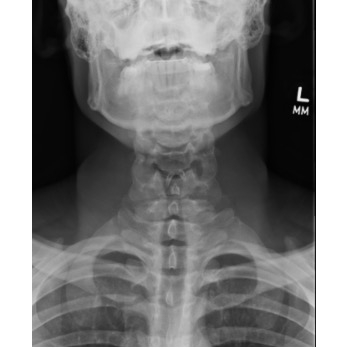

Odynophagia And Dyspnea In A College Basketball Player - Page #3 | |||